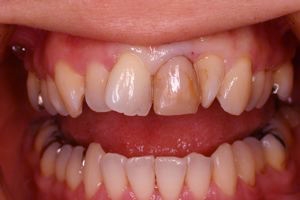

インセラム(オールセラミック)症例②

治療前治療前術前 治療後治療後術後 歯の尖端の透明感までよく再現できている。